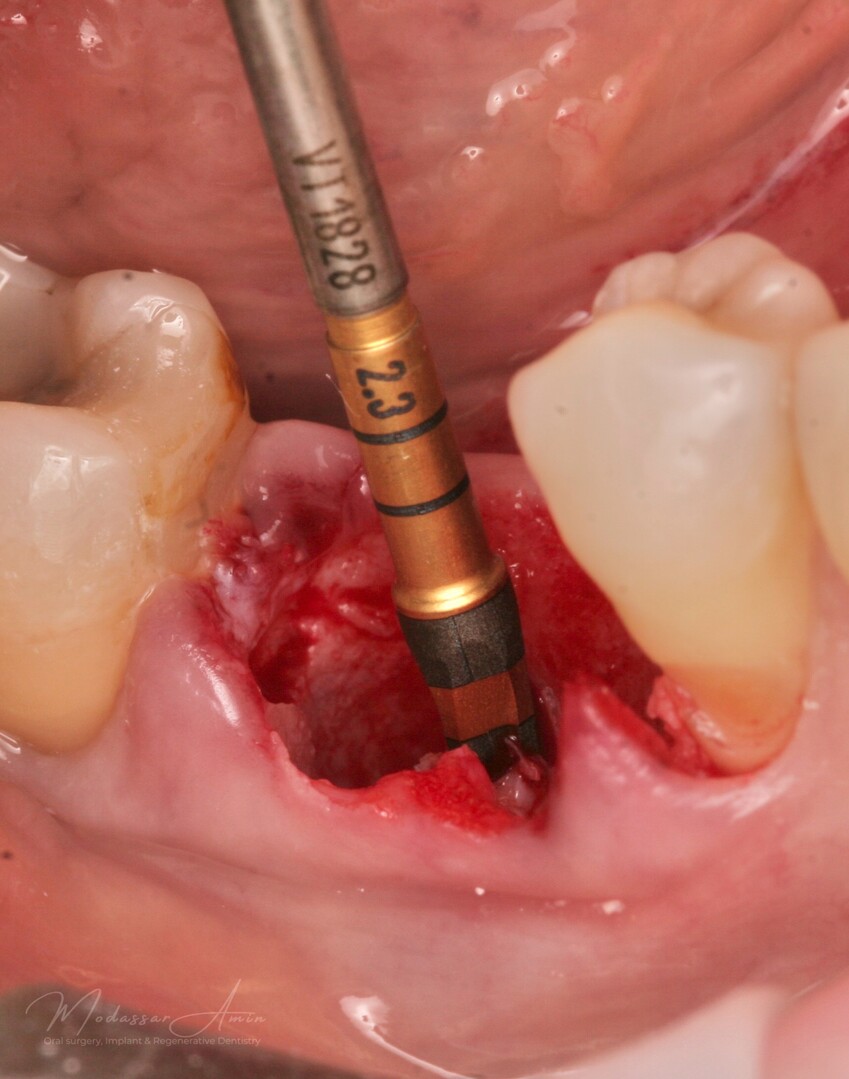

PATIENTFALL

"Pasienten presenterte med tann 46 som ikke kunne bevares grunnet en dyptgående infraksjon inn i furkasjonen. Forholdene lå til rette for en immediate implantatbehandling. Ved hjelp av Versah osseodensifikasjonsbor ble det interradikulære beinet ekspandert på en skånsom og forutsigbar måte, noe som ga høy primærstabilitet (>40 Ncm) til tross for en lokal bendefekt apikalt mesialt etter kronisk apikal periodontitt. Den gode stabiliteten muliggjorde bruk av SSA (Sealing Socket Abutment) for forsegling. På grunn av tynn bløtvevsfenotype bukkalt ble behandlingen supplert med bindevevstransplantat (CTG)"

Versah borr 2.3

Expanderat septum

God primär stabilitet på 40+ ncm